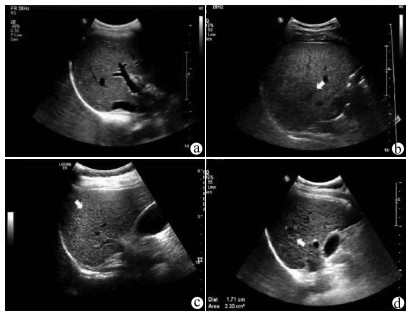

肝病超声诊断指南

中华医学会超声医学分会, 中国研究型医院学会肿瘤介入专业委员会, 国家卫生和健康委员会能力建设和继续教育中心超声医学专家委员会

2021, 37(8): 1770-1785. DOI: 10.3969/j.issn.1001-5256.2021.08.007

摘要(3068) HTML (6587) PDF (9311KB)(804)

摘要:

超声检查无创、实时、价廉,无辐射、便于反复进行,是最常用的肝脏影像学检查方法。近年来,超声检查新技术如超声造影、弹性成像发展迅速,可有效鉴别肝内占位性病变性质、评估肝纤维化和门静脉高压程度以及监测肝病治疗效果,在临床肝病及其介入治疗中发挥重要诊断价值。本指南规范了肝病多模态超声技术(灰阶超声、彩色多普勒超声、超声造影、弹性超声)检查的仪器调置、患者准备及医生检查方法;对肝脏弥漫性病变(炎性病变、纤维化、硬化)、多种占位性病变及肝病介入操作的多模态超声技术诊断标准进行了定义和规范,同时推荐了超声监测周期及肝脏疾病超声诊断报告书写规范。